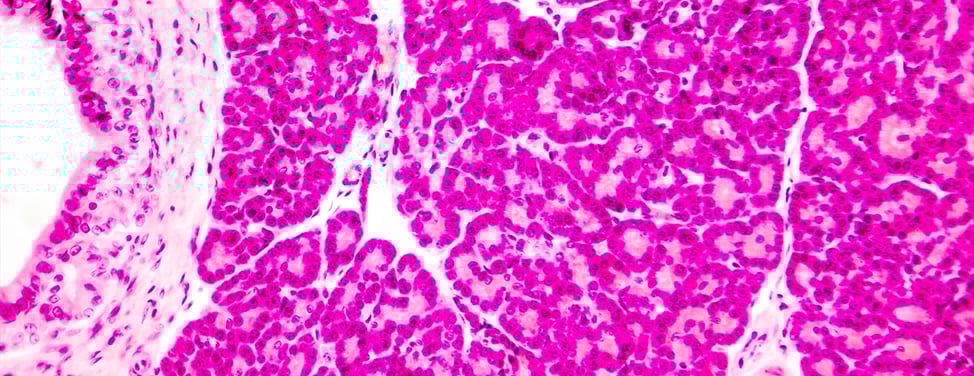

During an islet autotransplant, the patient's own islet cells are isolated from the removed pancreas. They are then put back into the patient, where they start producing insulin. The islet auto-transplant technique is a modification of an islet transplant procedure used to manage severe insulin-dependent (type 1) diabetes, in which islets are isolated from a deceased donor pancreas. In chronic pancreatitis, the patient’s own islets are used, eliminating the risk of tissue rejection.